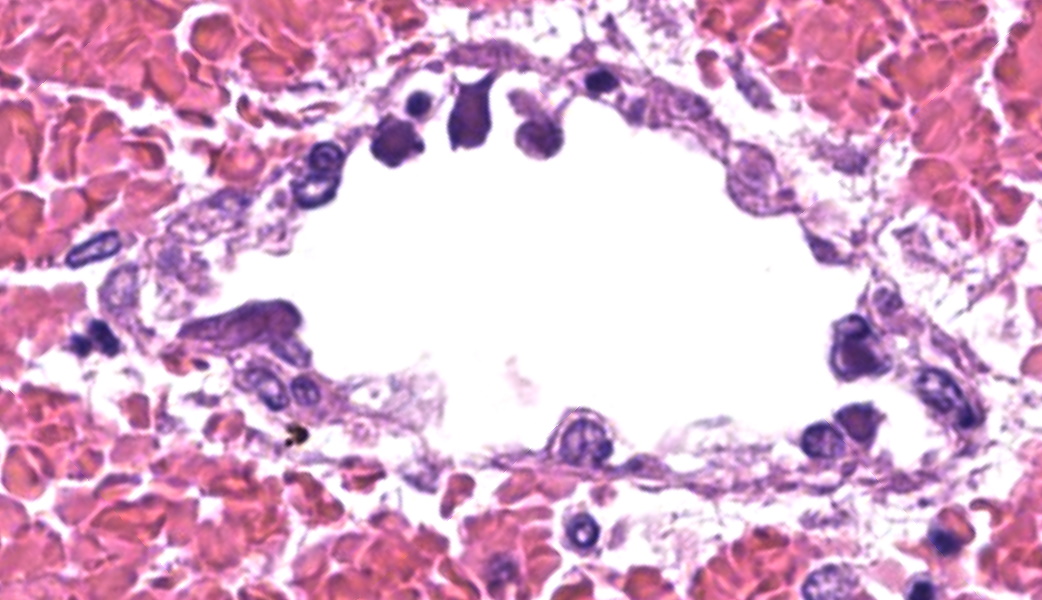

Throughout the cerebral gray matter, small caliber vessel walls were frequently obscured by mild to moderate amounts of eosinophilic, fibrillar, proteinaceous material and hemorrhage. Endothelial cells frequently contained large, eosinophilic, intranuclear inclusions which peripheralize chromatin. Affected vessels were frequently cuffed by moderate numbers of macrophages and lymphocytes, and there were frequent, small areas of hemorrhage spilling into the adjacent tissue. The meninges overlying the cerebellum were moderately expanded by lymphocytes and macrophages, and endothelial cells frequently contained intranuclear inclusions similar to those found in the cerebral vessels.

Severe, multifocal, acute, histiocytic vasculitis and meningitis with cerebral hemorrhage and intranuclear viral inclusions.

Cerebrum: Vasculitis, neutrophilic and lymphocytic, subacute, multifocal to coalescing, marked, with fibrin thrombi, lymphohistiocytic meningitis, and endothelial intranuclear viral inclusions.